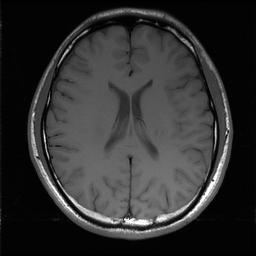

Magnetic resonance imaging serves as an essential tool for clinical diagnosis. However, it suffers from a long acquisition time. The utilization of deep learning, especially the deep generative models, offers aggressive acceleration and better reconstruction in magnetic resonance imaging. Nevertheless, learning the data distribution as prior knowledge and reconstructing the image from limited data remains challenging. In this work, we propose a novel Hankel-k-space generative model (HKGM), which can generate samples from a training set of as little as one k-space data. At the prior learning stage, we first construct a large Hankel matrix from k-space data, then extract multiple structured k-space patches from the large Hankel matrix to capture the internal distribution among different patches. Extracting patches from a Hankel matrix enables the generative model to be learned from redundant and low-rank data space. At the iterative reconstruction stage, it is observed that the desired solution obeys the learned prior knowledge. The intermediate reconstruction solution is updated by taking it as the input of the generative model. The updated result is then alternatively operated by imposing low-rank penalty on its Hankel matrix and data consistency con-strain on the measurement data. Experimental results confirmed that the internal statistics of patches within a single k-space data carry enough information for learning a powerful generative model and provide state-of-the-art reconstruction.